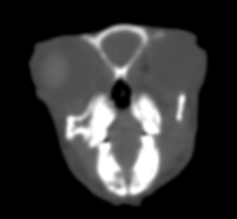

CT検査

体の内部を輪切り状に撮影し、コンピューター処理で立体画像として表示する検査です。Ⅹ線検査・超音波では見えにくい部分まで可視化できます。上記2つの検査(Ⅹ線検査・超音波)は保定(ウサギが動かないように抑えておく)必要があり、多少なりとストレスがかかってしまいます。動物のCT検査は麻酔下というイメージが多いですが、動物病院によっては無麻酔下で評価してくれる所もあります。※麻酔下と比べると精度は落ちます。ウサギはじっとしてくれることが多いので、専用のもしくは持参したケージそのままでパッと撮影可能です。Ⅹ線検査で記載したものをより細かく観察が可能になります。特にⅩ線検査ではまだわからないレベルの肺腫瘍や、歯の根尖部とその周囲組織や骨の変性の詳細な確認も可能です。胸部や腹部の詳細評価だけではなく、Ⅹ線検査や超音波では評価が難しい鼻腔内や中耳も同時に評価できることもメリットです。